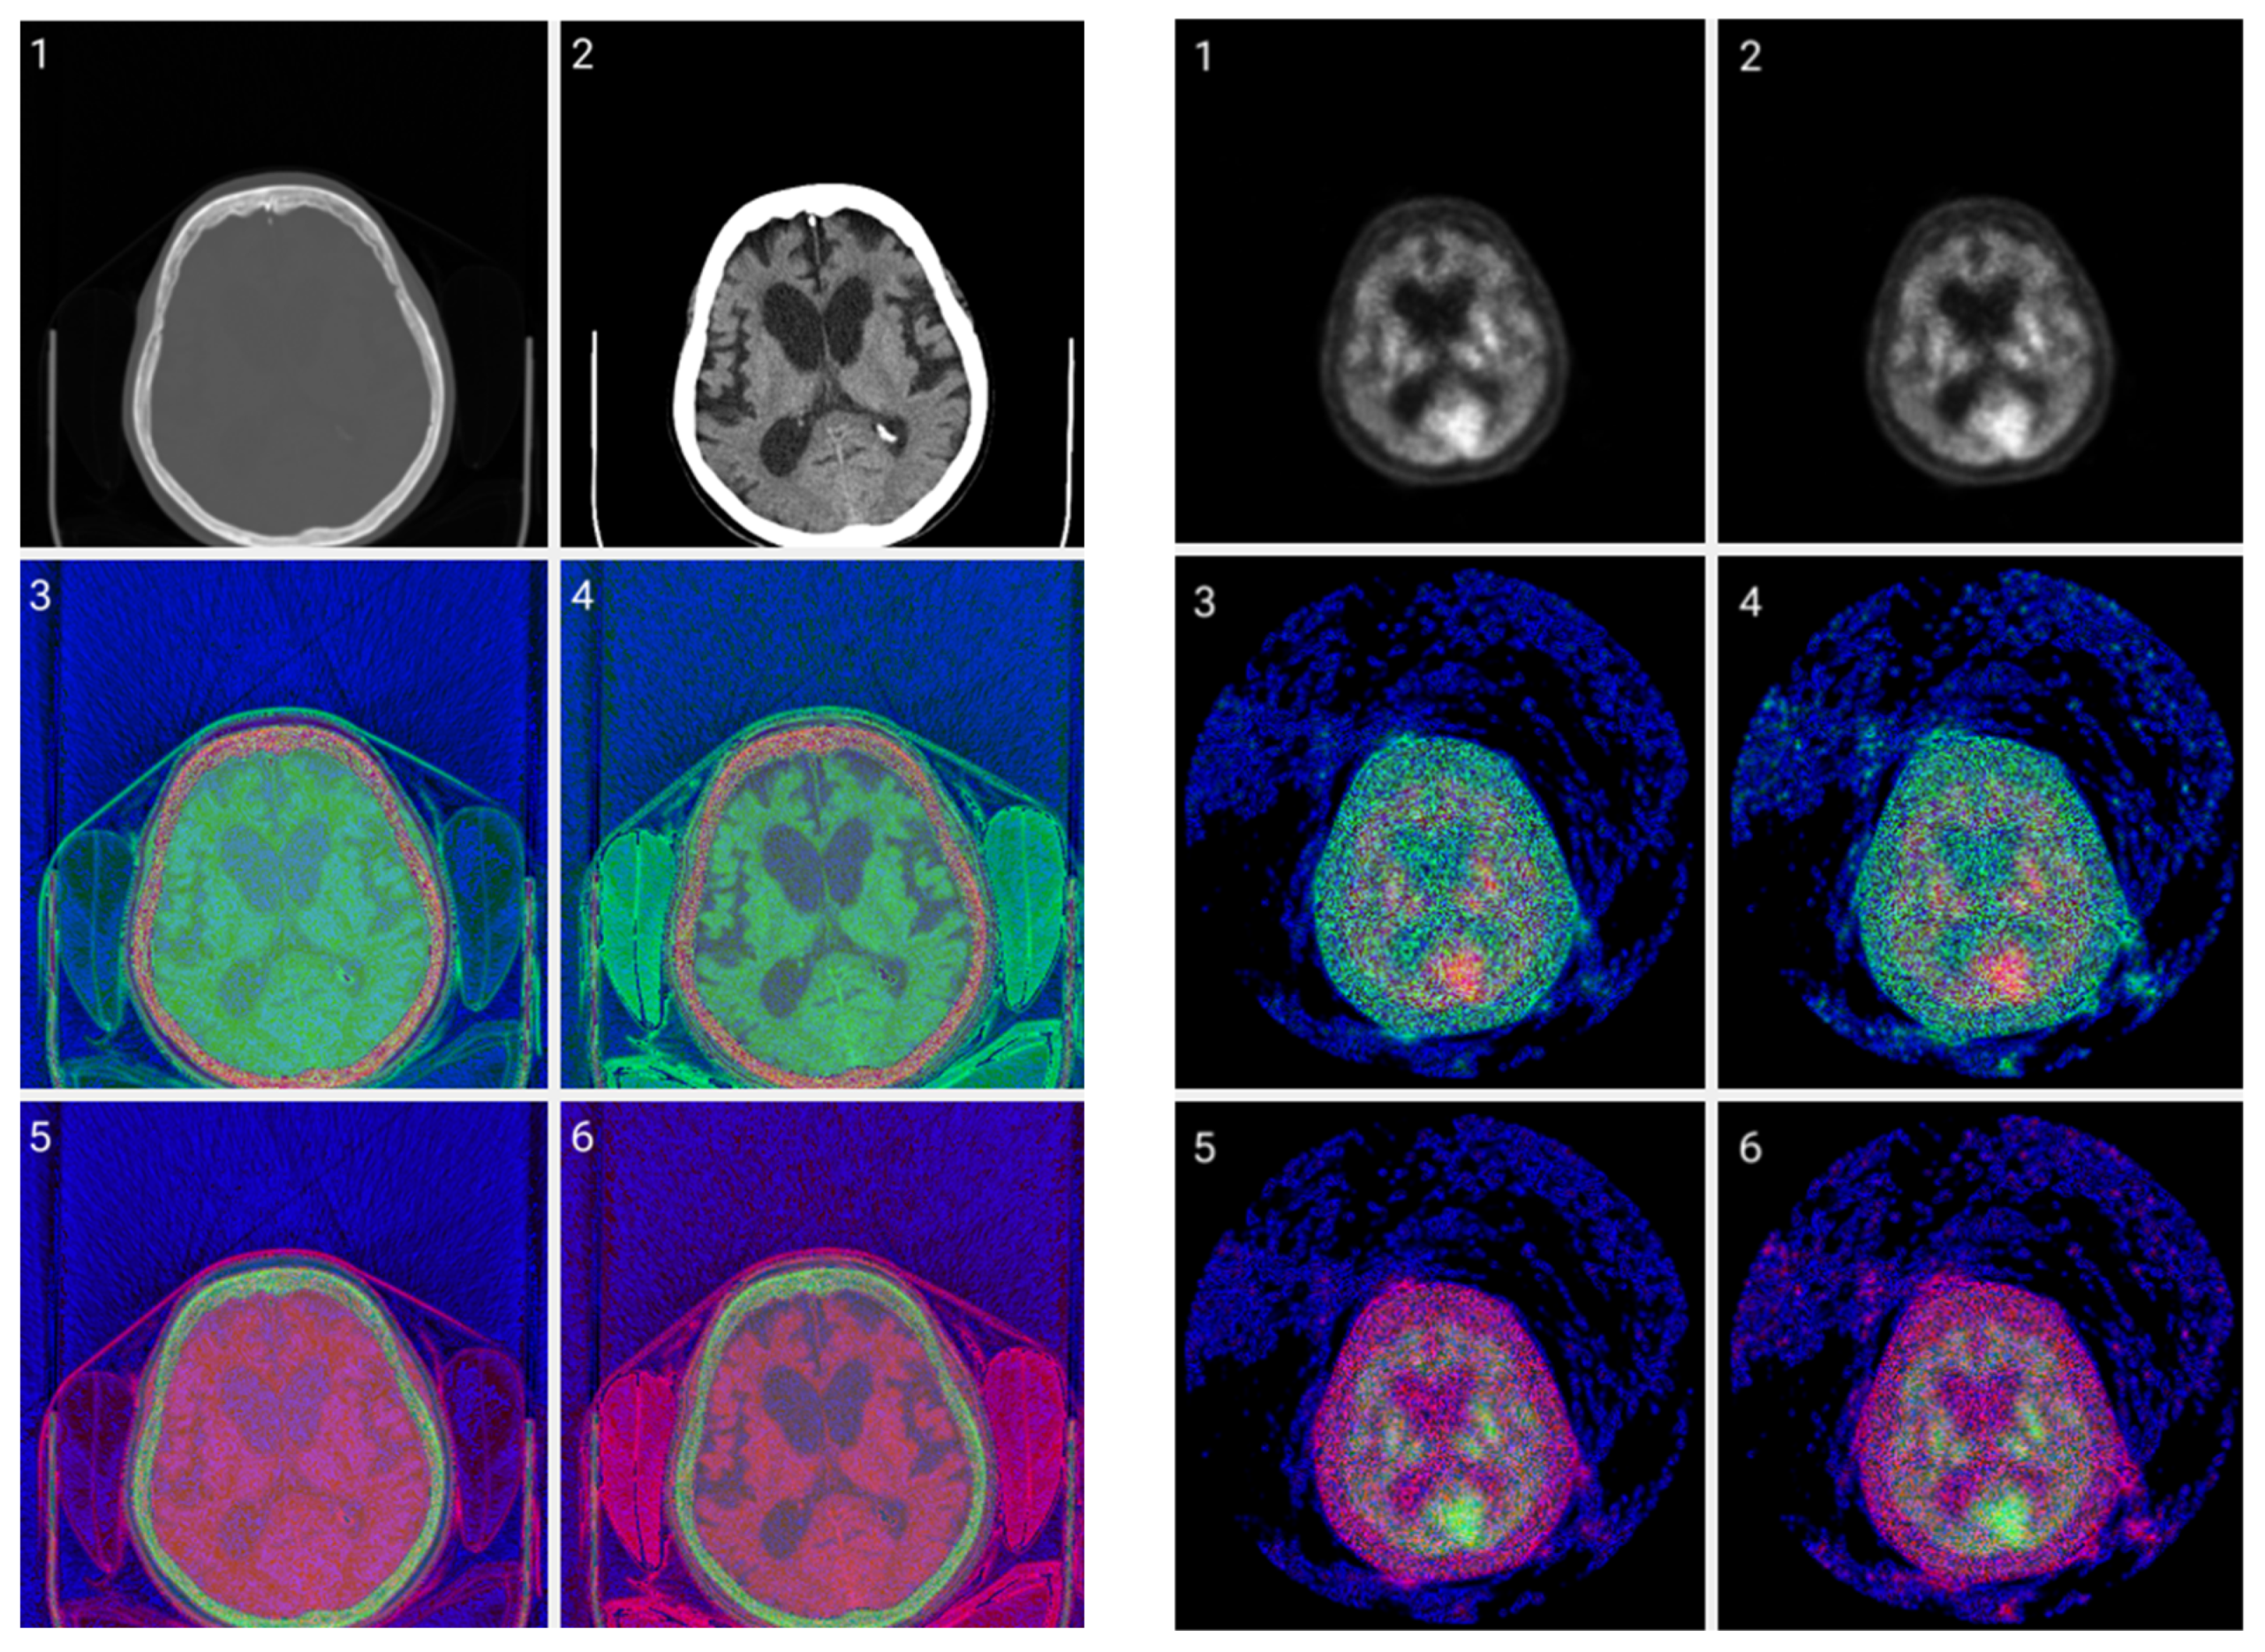

3.2. Colormap Folding Application

2.3. Method 2: Folding Colormap